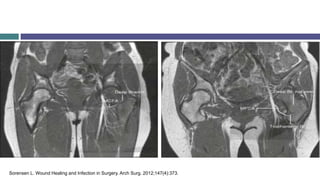

Sorensen L. Wound Healing and Infection in Surgery. Arch Surg. 2012;147(4):373.

Sorensen L. WoundHealing and Infection in Surgery. Arch Surg. 2012;147(4):373.

• #10 Fractures of the femoral neck will interrupt completely the blood supply from the diaphysis and, should the retinacula also be torn, avascular necrosis of the head will be inevitable. The nearer the fracture to the femoral head, the more tenuous the retinacular blood supply and the more likely it is to be disrupted. Hip resurfacing can also disrupt the retinacular blood flow. This is because as part of the procedure they sacrifice the medial circumflex femoral artery which branches two of the three groups of the retinacular arteries: posterior inferior - posterior superior. This can lead to a loss of blood supply and avascular necrosis. This only occurs if the intraosseous blood supply is weak.

• #11 4. Sorensen L. Wound Healing and Infection in Surgery. Arch Surg. 2012;147(4):373.